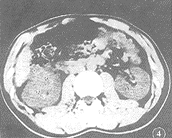

圖1圖1 左腎未成熟膿腫。增強掃描左腎中上極後方類圓形低密度灶,穿破腎包膜,擴展至腎後旁間隙,在此間隙內的病灶液化壞死明顯